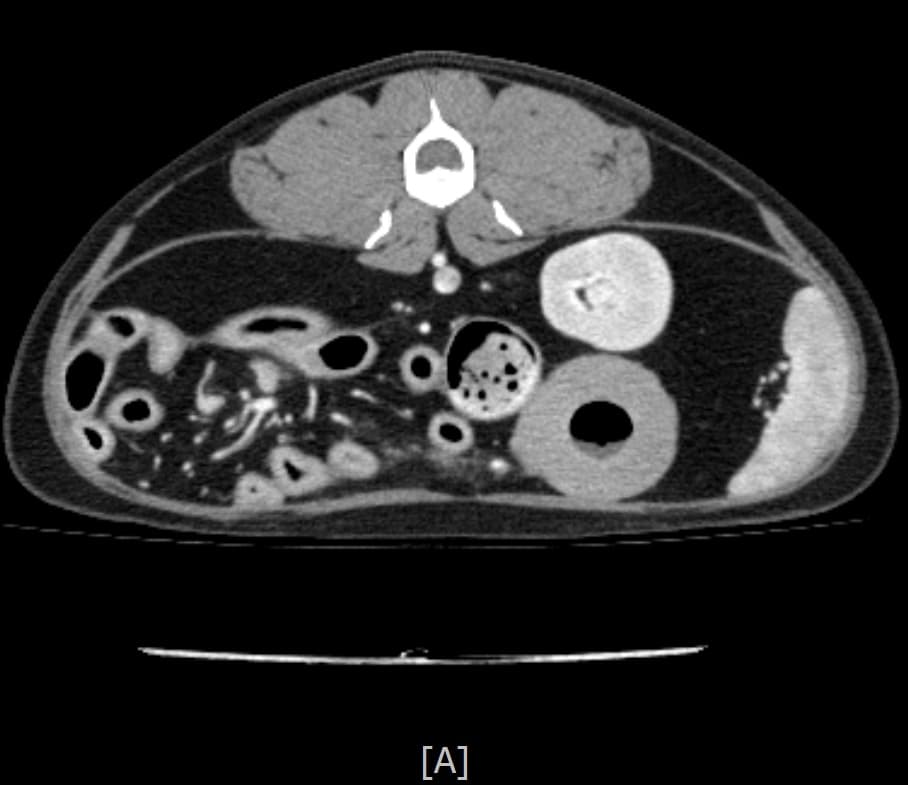

동탄 1 신도시 최초 Aquilion CX/128 slice CT를 동물병원에 도입하였습니다. 최고 사양 CT 모델 Aquilion CX/128 slice를 활용하여 0.5 mm의 얇은 128개의 단면 영상을 신속히 획득 할 수 있어 마취 시간을 단축시킬 수 있습니다. 또한, 128 슬라이스의 고화질의 CT 영상을 통해 영상 왜곡을 최소화하고 X-ray에서는 확인하기 힘든 5 mm 이하의 미세 병변도 확인이 가능하여 정확한 진단을 할 수 있습니다. 심화 진단이 필요한 경우, 조영제 인젝터를 통한 동맥기 촬영으로 종양 유래 확인, 간 질환 진단, 심혈관계 진단이 용이합니다. 저희 동탄시티동물의료센터에서는 본원 환자뿐 아니라 1차 동물 병원과의 CT 촬영 의뢰 시스템을 통해서 원활한 협진이 가능하도록 최선을 다하고 있습니다.

0164 채널 CT 촬영을 통해서 신속하게 고화질 영상을 얻어, 종양 유래 확인 및 전이 평가, 간문맥단락증(PSS), 선천적 뼈 기형과 같은 심화된 진단을 할 수 있습니다.

64채널 검출기 시스템 128

슬라이스 이미징 능력

고속 스캔 및 높은 해상도 제공

저선량 기술 적용으로 환자 방사선 노출 감소

흉복부, 골격계 전반의 선명하고 우수한 영상을 저선량으로 촬영이 가능